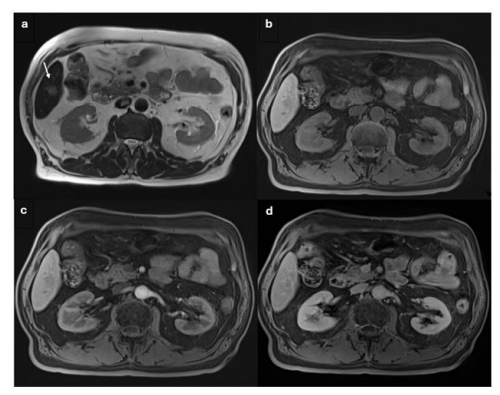

Vascular Endothelial Growth Factor (VEGF): Elevated by 35.9%, VEGF was associated with increased angiogenesis, essential for tumor growth and metastasis, indicating higher malignant potential (Figure #3).

Liquid Biopsy Findings in LI-RADS 4 LesionsCirculating Tumor Cells (CTCs): CTCs were detected in 17.85% of patients with LI-RADS 4 lesions. The presence of CTCs in the bloodstream is a critical indicator of tumor spread and metastasis. In this cohort, patients with detectable CTCs were considered to be at high risk for aggressive HCC, and this finding significantly influenced treatment decisions.The detection of CTCs correlated well with the imaging characteristics of LI-RADS 4 lesions, supporting the probable HCC classification.

Circulating Tumor DNA (ctDNA): ctDNA was elevated in 32.14% of patients with LI-RADS 4 lesions. ctDNA reflects the presence of tumor-specific genetic mutations in the bloodstream, and its detection provided molecular confirmation of malignancy. Patients with elevated ctDNA levels were more likely to have confirmed HCC upon histopathological examination. The combination of elevated ctDNA and serum biomarkers such as AFP, HGF, and VEGF significantly strengthened the case for malignancy in LI-RADS 4 patients (Figure #4).

Imaging Findings and Serum Biomarkers in LIRADS 4 Lesions

For LI-RADS 4 lesions, the imaging characteristics suggest a high probability of malignancy, often indicative of early HCC. The lesions typically show more pronounced arterial phase hyperenhancement (APHE), with late-phase nonperipheral washout and the presence of enhancing capsule.

Serum biomarker findings for LI-RADS 4 patients showed that 25% had elevated AFP levels, with a mean value of 211 ng/mL. AFP-L3 levels were elevated in 46.42% of patients, with additional increases in LDH, HGF, and IL-6.